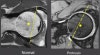

MRI는 단독으로 시행하기도 하지만, 관절 조영 MRI를 시행할 경우 비구순 및 관절 연골 손상 등을 파악하기 쉽고, 대퇴골두-경부 경계 형태를 파악하는데 더 용이합니다.

비구순 파열이나 관절연골 손상시 MRI는 false 음성으로 나올 수 있으므로 MR 관절조영술을 하는 것이 바람직합니다.

MRI : Articular cartilage

MRI : Cartilage delamination